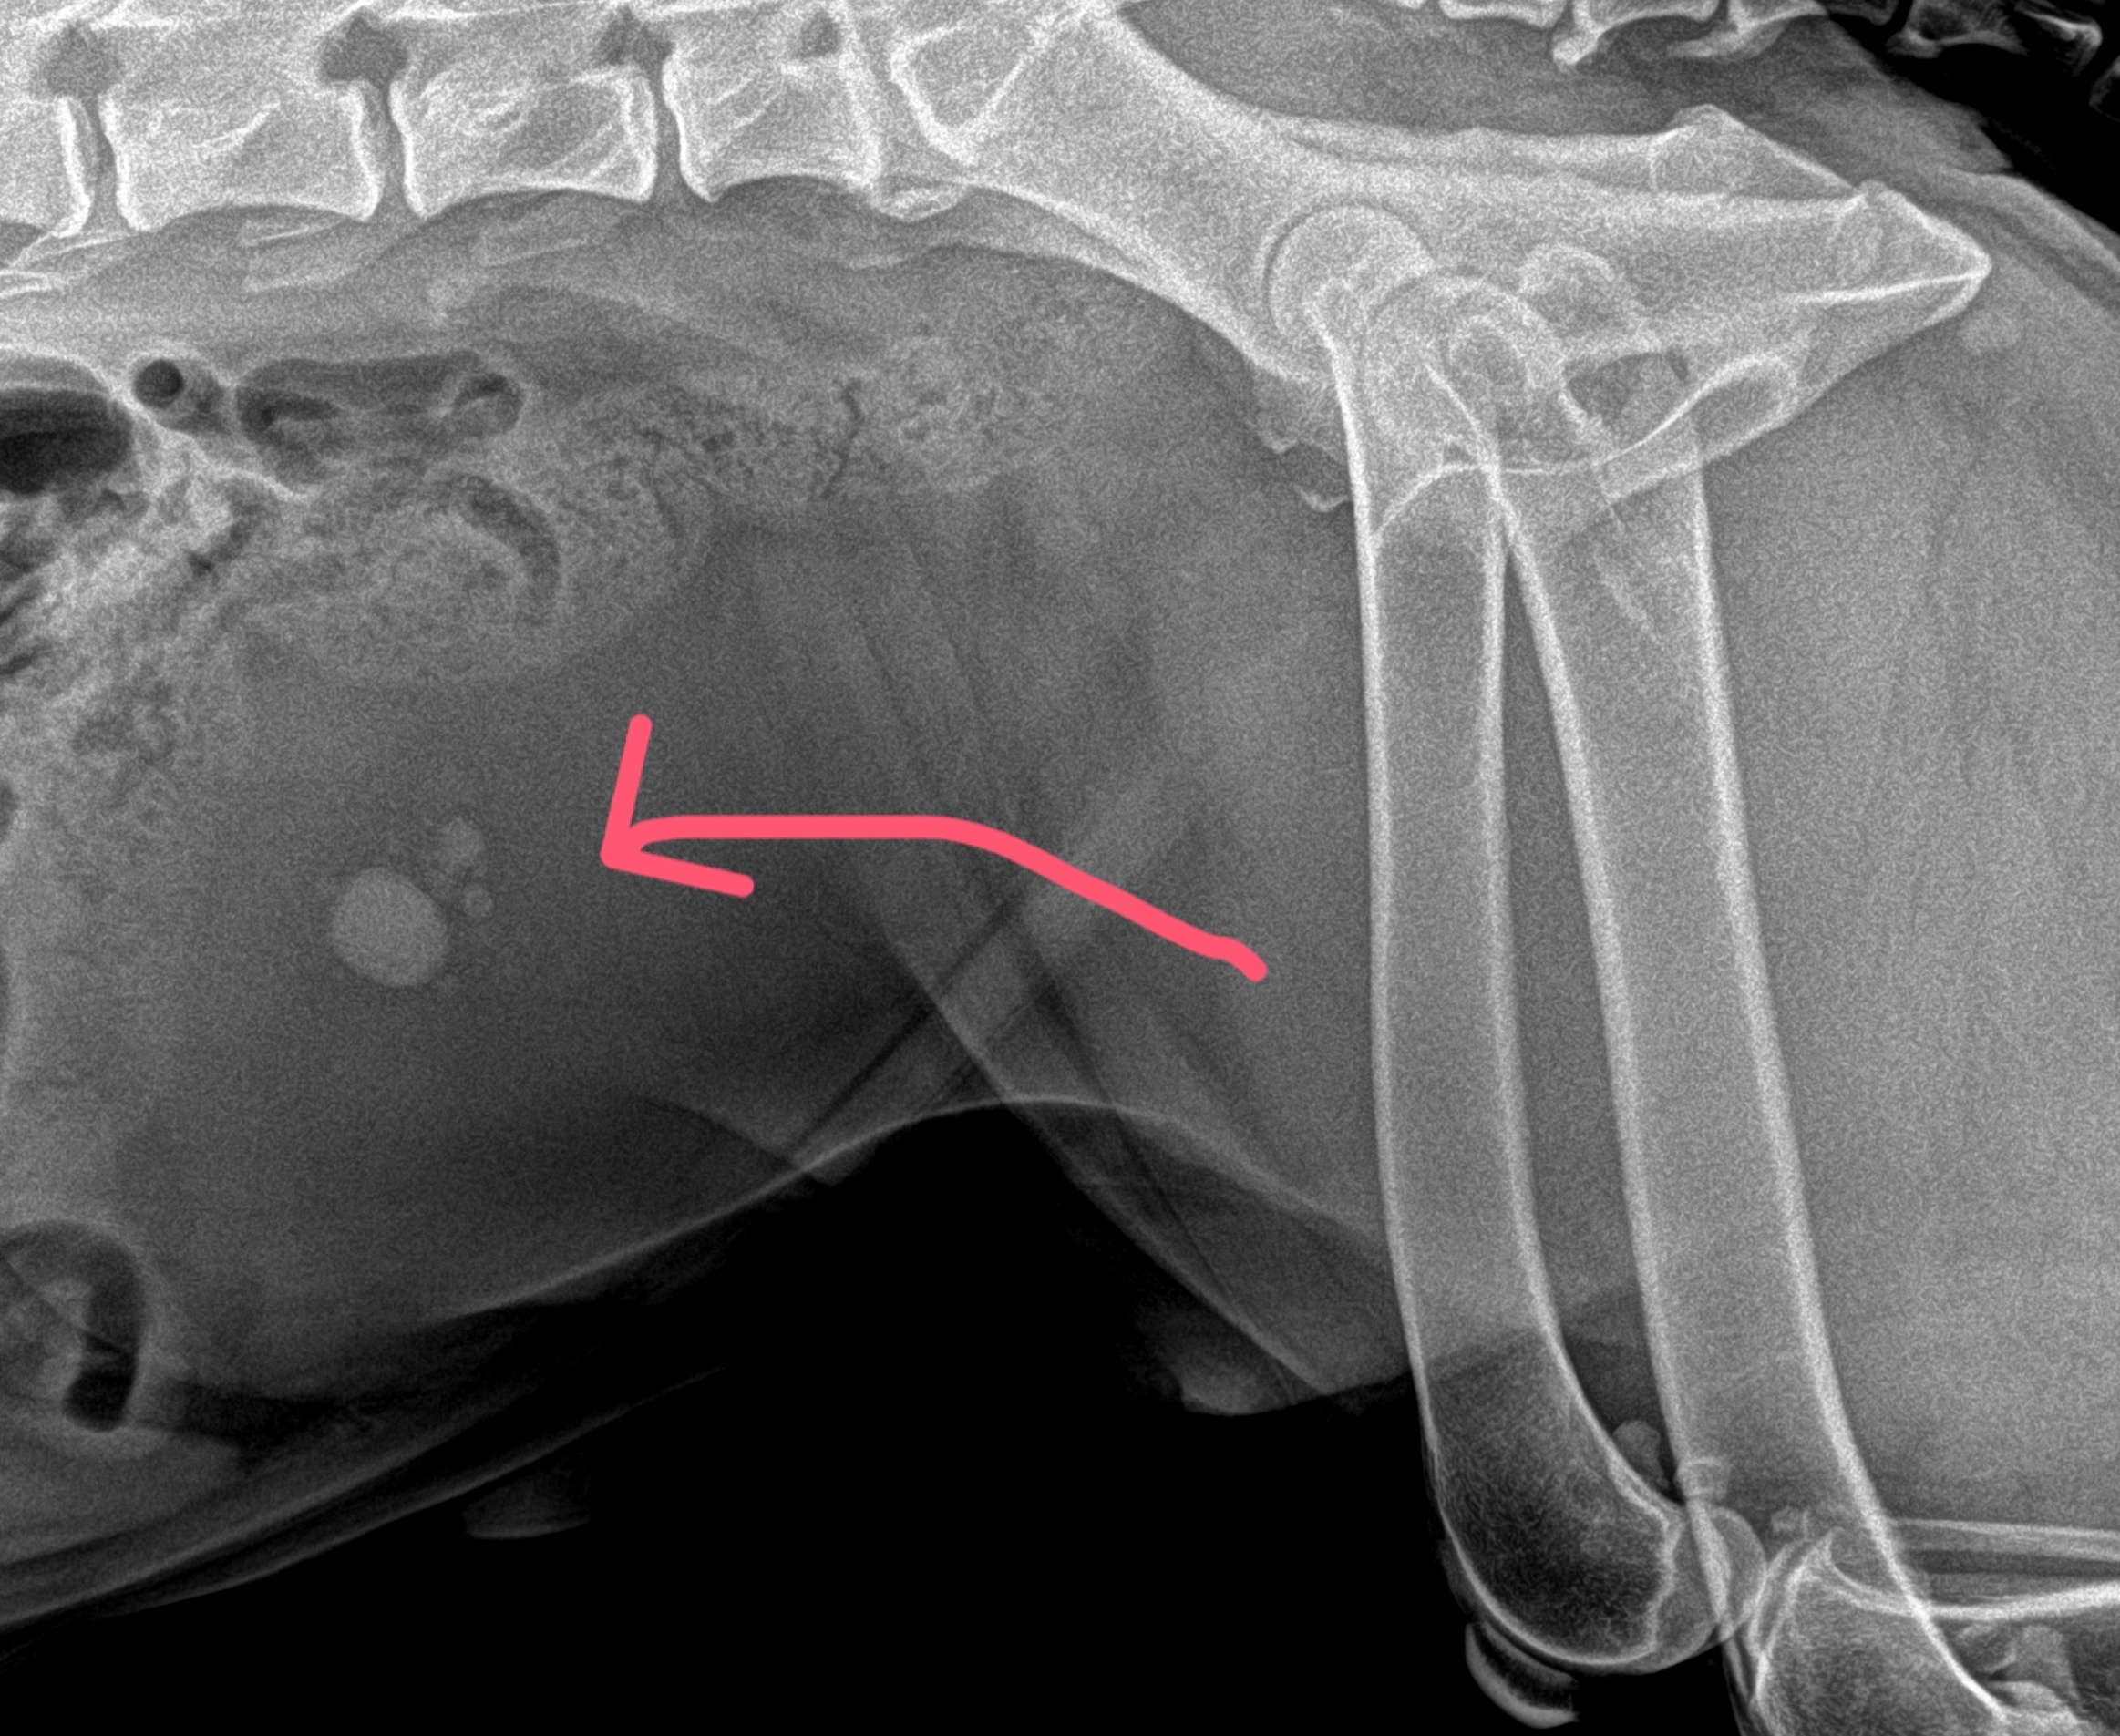

Драгоценный улов: как мы достали камни из мочевого пузыря собаки без операции

Мы достали огромное количество камней из мочевого пузыря собаки БЕЗ ОПЕРАЦИИ 😱

Как такое возможно ? Только благодаря литотриптору

Литотриптор — это современное оборудование, которое используется для безоперационного разрушения камней в мочевом пузыре и почках у наших пушистиков. 🐶🐱 🔍